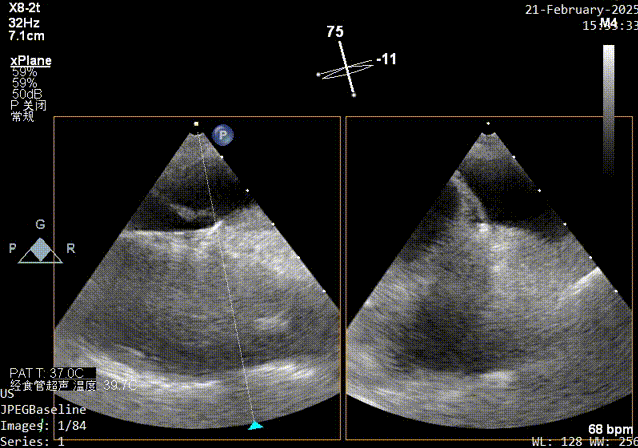

术前发泡实验超声影像

Xplane超声影像